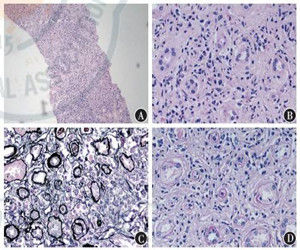

腎小管間質纖維化的病理表現為:腎間質單核細胞、淋巴細胞的浸潤,引起炎症性反應,腎小管足細胞受損,表形轉化、萎縮,間質成纖維細胞活化增殖以及細胞外基質(ECM)過度沉積、瘢痕硬化形成。

在腎小管-間質瘢痕硬化形成機制中,腎間質的炎性細胞浸潤、炎症性反應、腎小管足細胞受損、表型轉化,腎間質成纖維細胞的活化與增殖和細胞外基質的過度沉積、導致間質瘢痕硬化的形成。